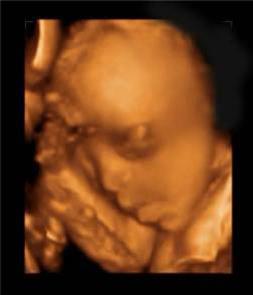

擁有雙胞胎寶寶父母當然都很幸福,雖然養育兒女付出了雙份的辛苦,但同時也收穫了雙份的歡樂。  他們在媽媽肚子的時候就已經頻頻互動,有時候還會親吻,打架!超級萌,超級感人!